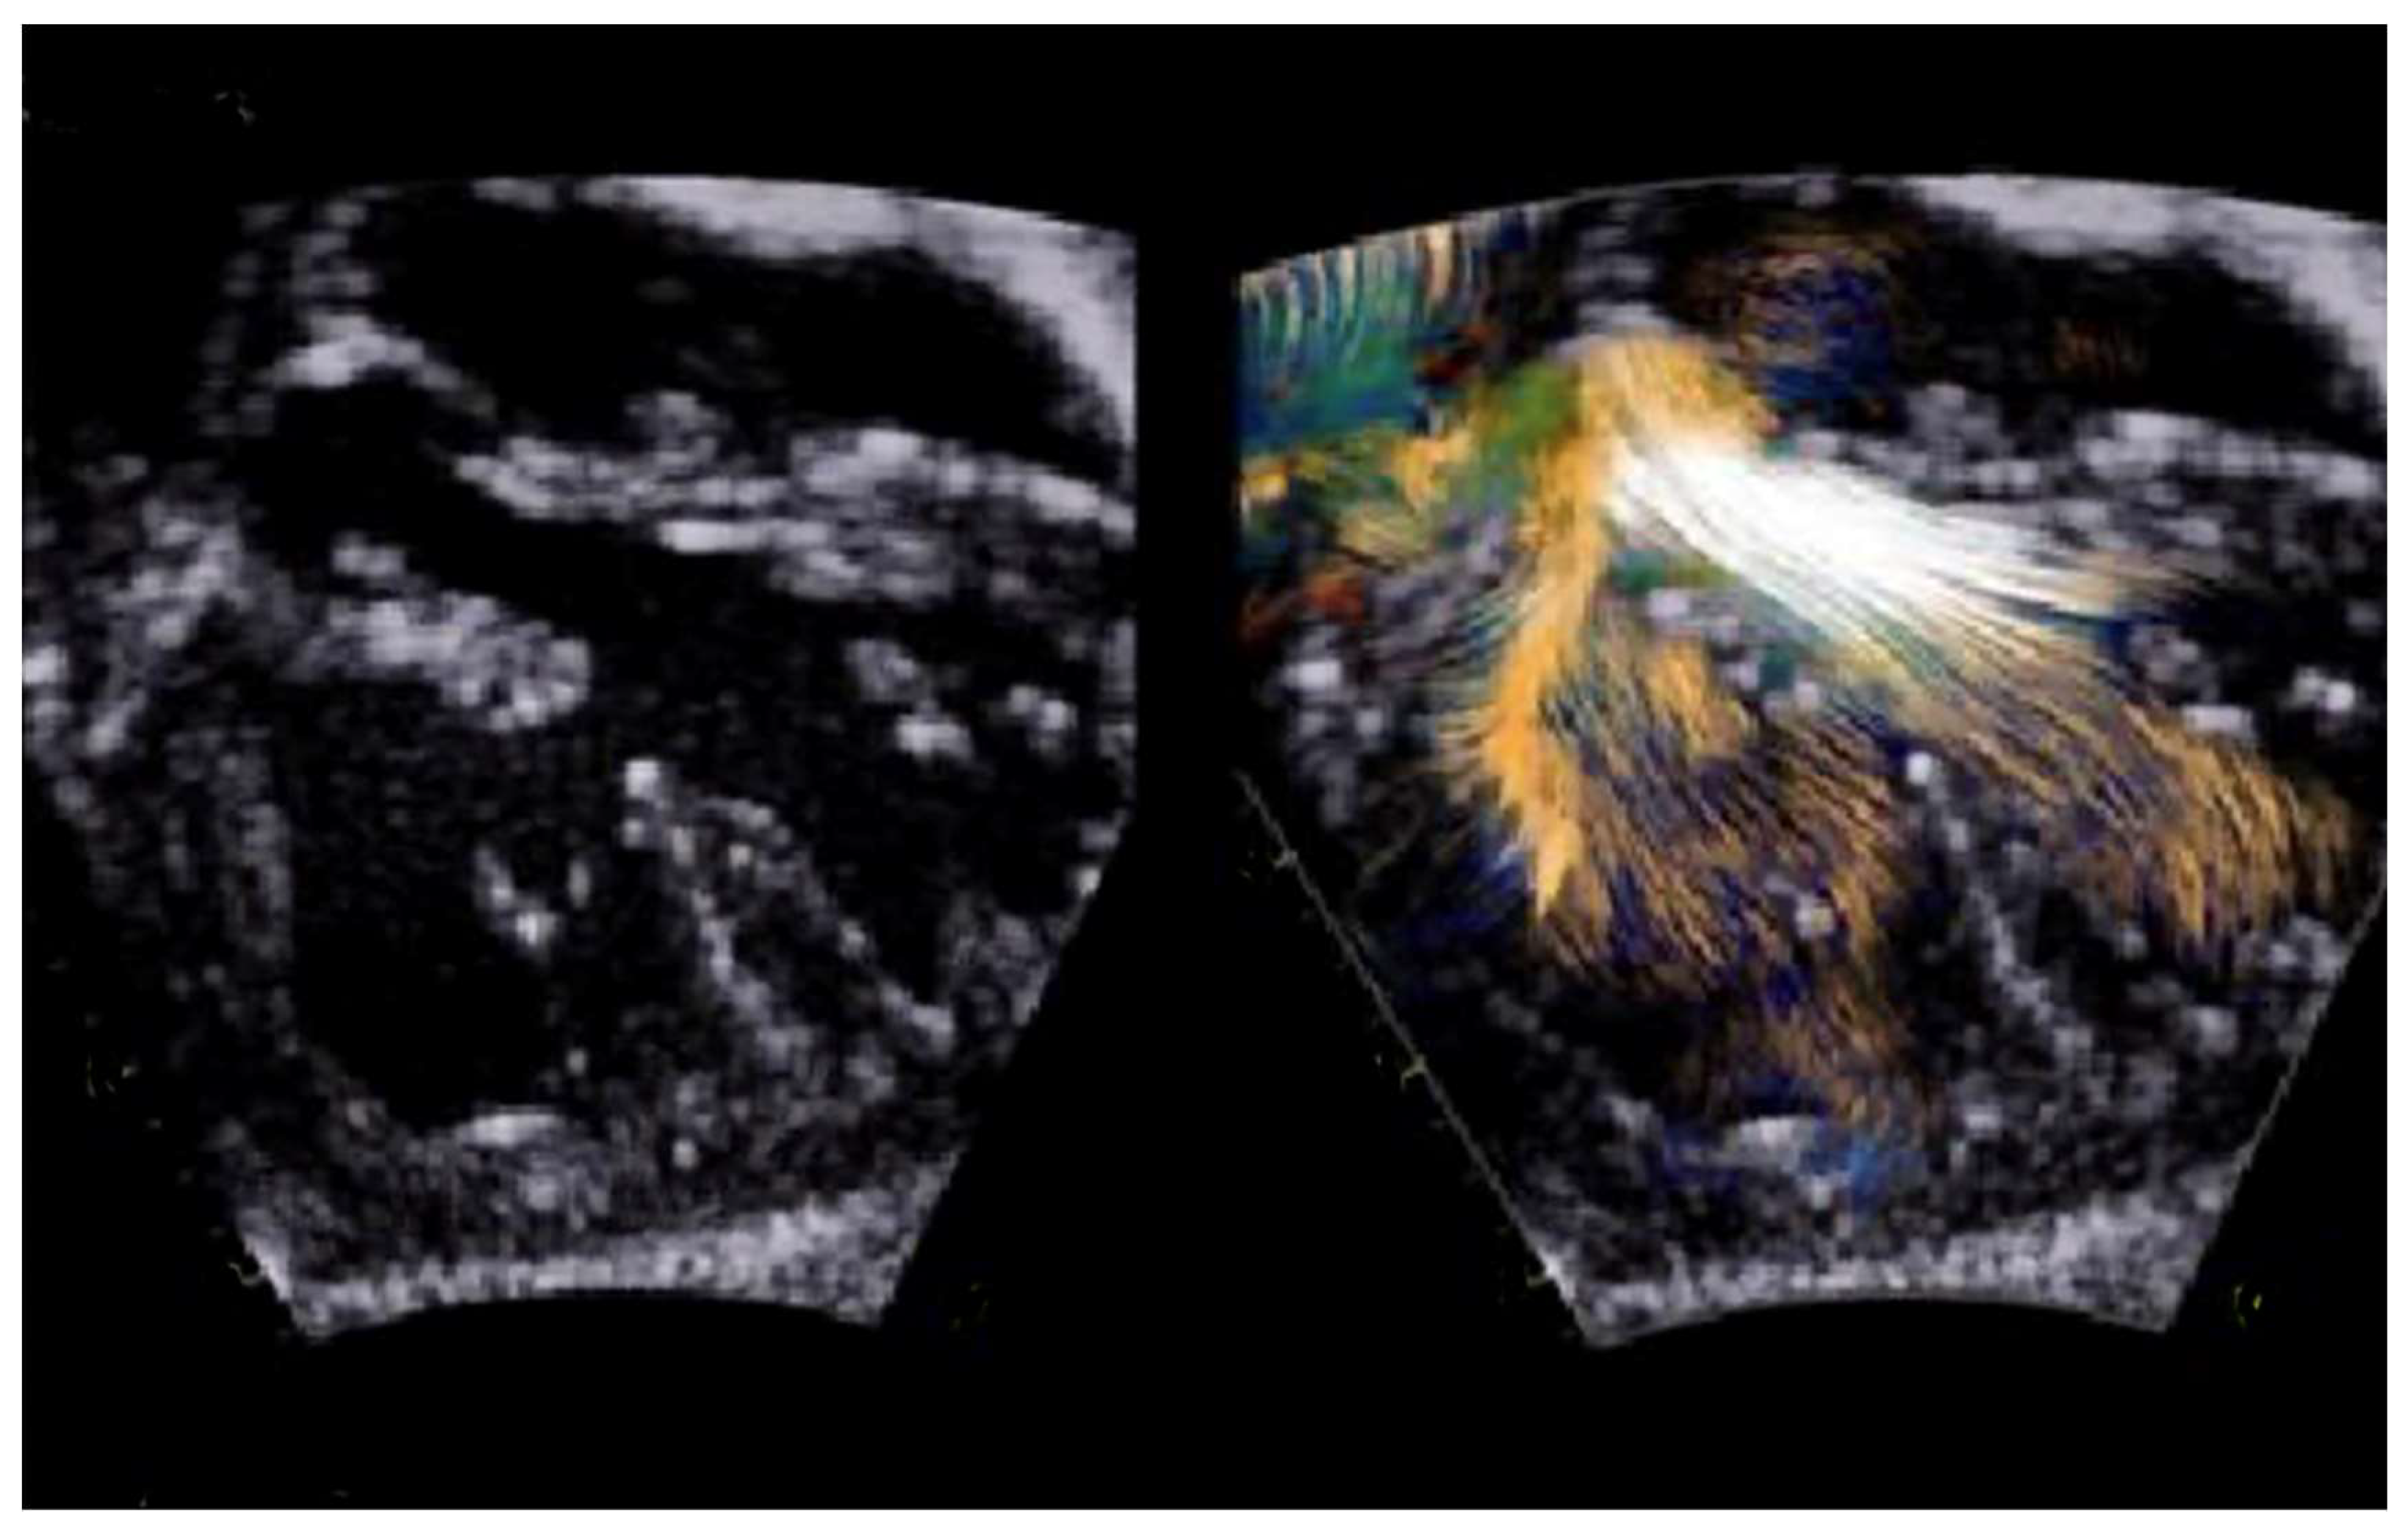

- Borrelli, N.; Avesani, M.; Sabatino, J.; Ibrahim, A.; Josen, M.; Paredes, J.; Di Salvo, G. Blood Speckle Imaging: A New Echocardiographic Approach to Study Fluid Dynamics in Congenital Heart Disease. Int. J. Cardiol. Congenit. Heart Dis. 2021, 2, 100079. [Google Scholar] [CrossRef]